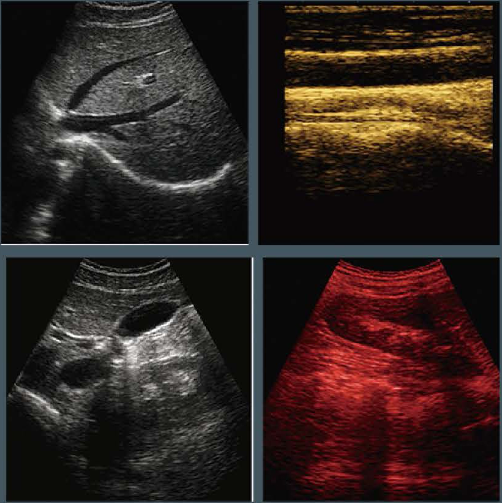

Product name : Ultrasound Machine for Pregnancy

Display mode : B,2B,4B,BM,M

Main Application : Abdomen, Pregnancy

Application

Abdomen / Obstetrics / Gynecology /

Urology / Andrology / Small Parts / Vascular /

Pediatrics / Musculoskeletal

Imaging

Human Pregnancy Examination Trolley Ultrasound Scanner 24 Month Warranty Images |